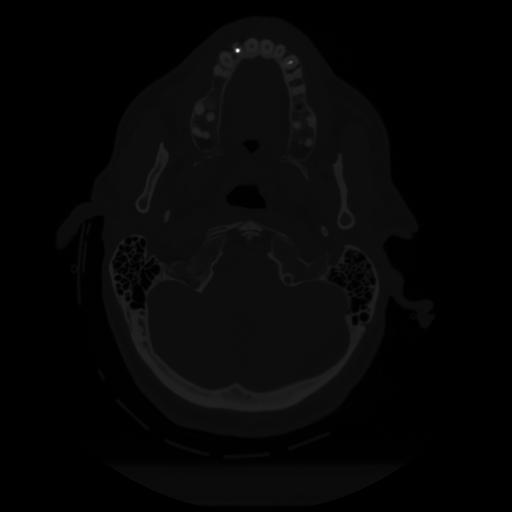

12 P.BLANDAS,,Vol,0.5,P.BLANDAS,,